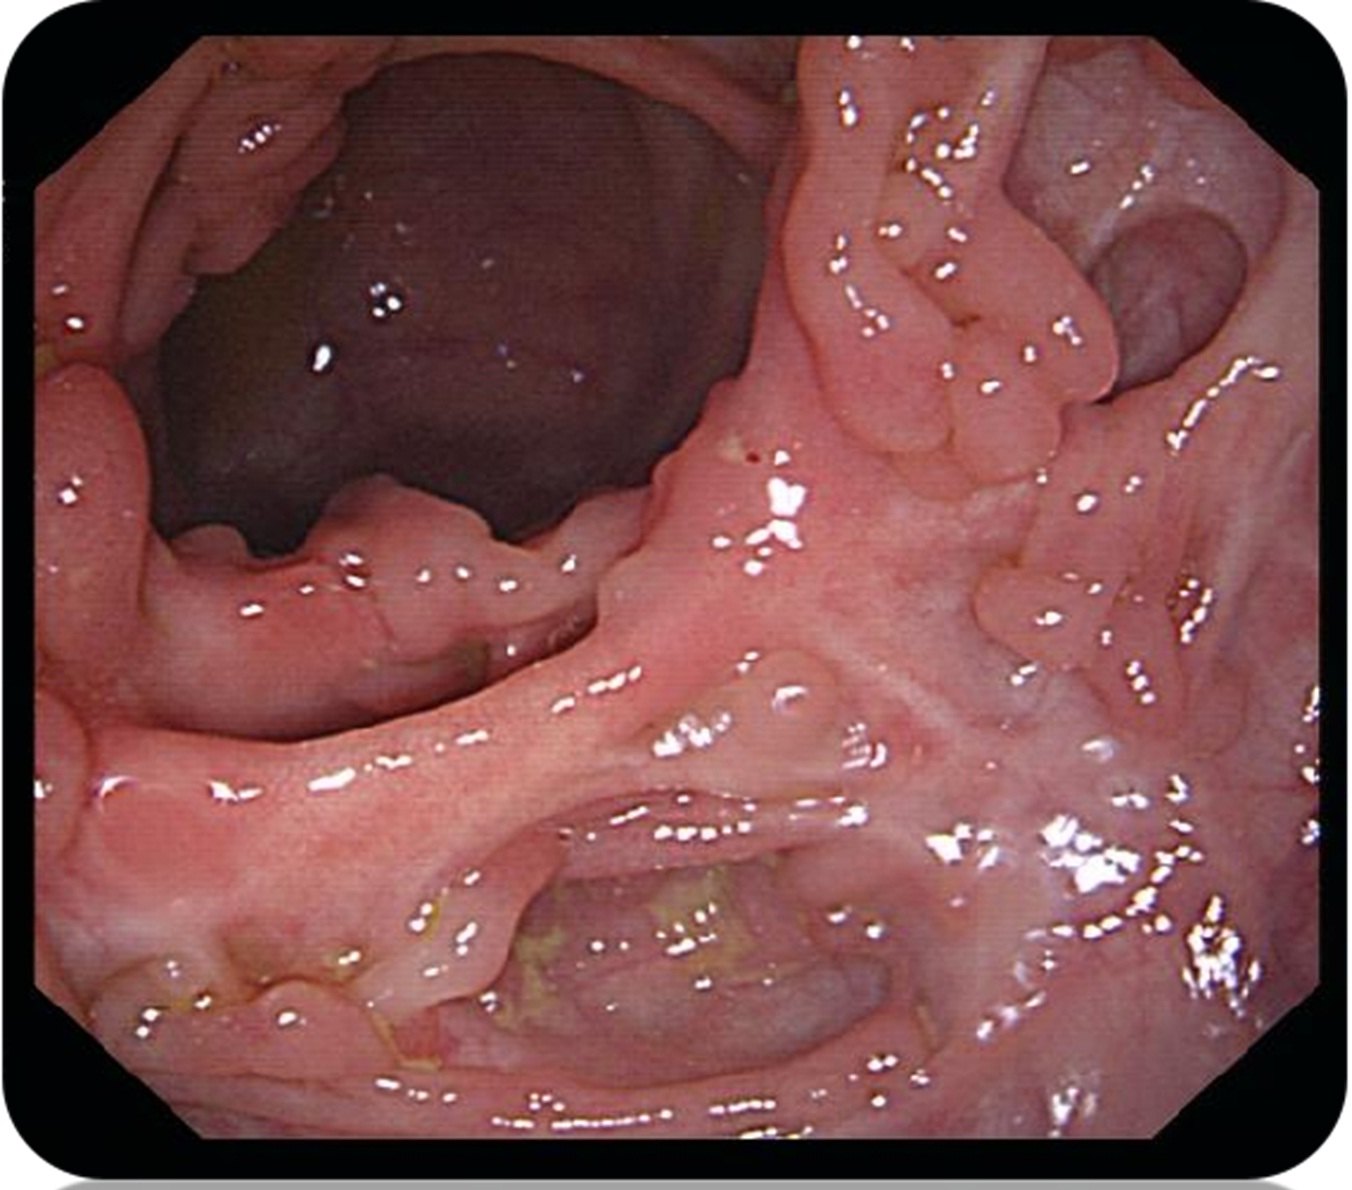

这是克罗恩病最常见的临床表现之一。患者主要出现腹泻、腹部不适、便血等消化系统炎症反应。在这种类型中,肠道黏膜受损严重,伴随着溃疡形成。此外,还可能出现贫血、体重下降等全身性表现。

2.狭窄型(stricturing type)

这是克罗恩病的进展阶段之一。患者在长期慢性炎症作用下,肠道受到持续性的纤维化和结构改变。这导致肠道管腔变窄,并可能出现肠梗阻的症状,如腹痛、呕吐等。此时,手术干预可能是必要的治疗方式。